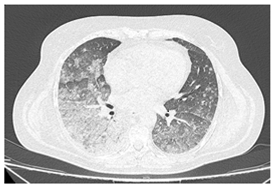

| Type of SARD-ILD | HRCT Features | Axial HRCT Images in Patients with SARD-ILD | Description of HRCT Images in Patients with SARD-ILD |

| IIM-ILD | NSIP or OP. | ![]() | The appearance of OP is frequently encountered in IIM-ILD patients. It is characterized by ground glass areas alternating with areas of condensation, often with a perilobular distribution. OP can overlap with NSIP, leading to exacerbations of ILD, or it may present as the initial pattern. |